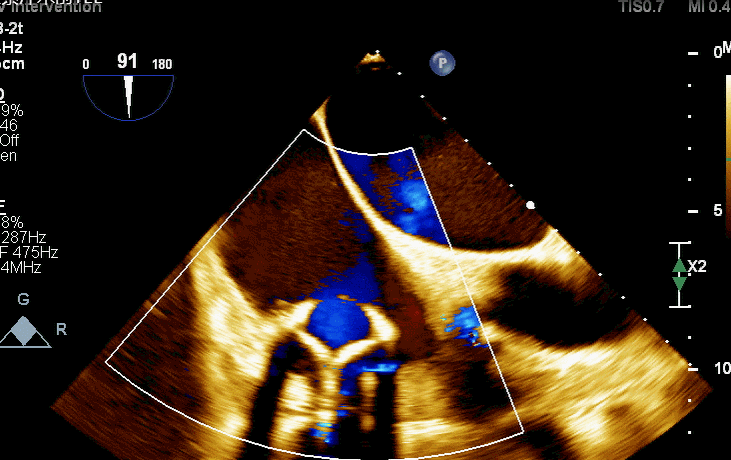

术后TV生物瓣活动良好

术后三维超声同时显示MV机械瓣及新的TV生物瓣